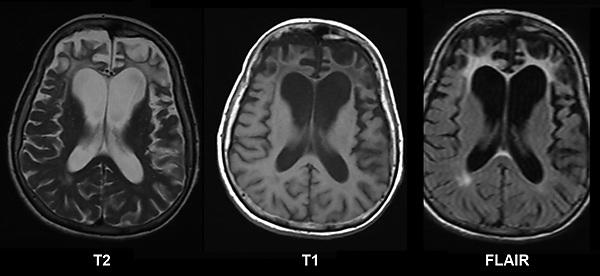

При гистологическом исследовании ткани головного мозга в нейронах обнаруживаются необычные включения. Пирамидные нейроны набухшие, содержат цитоплазматические тельца Пика. Толщина серого вещества снижена, граница между серым и белым веществом размыта. Отмечается расширение желудочков (преимущественно передних рогов боковых желудочков) и субарахноидального пространства, углубление борозд полушарий.